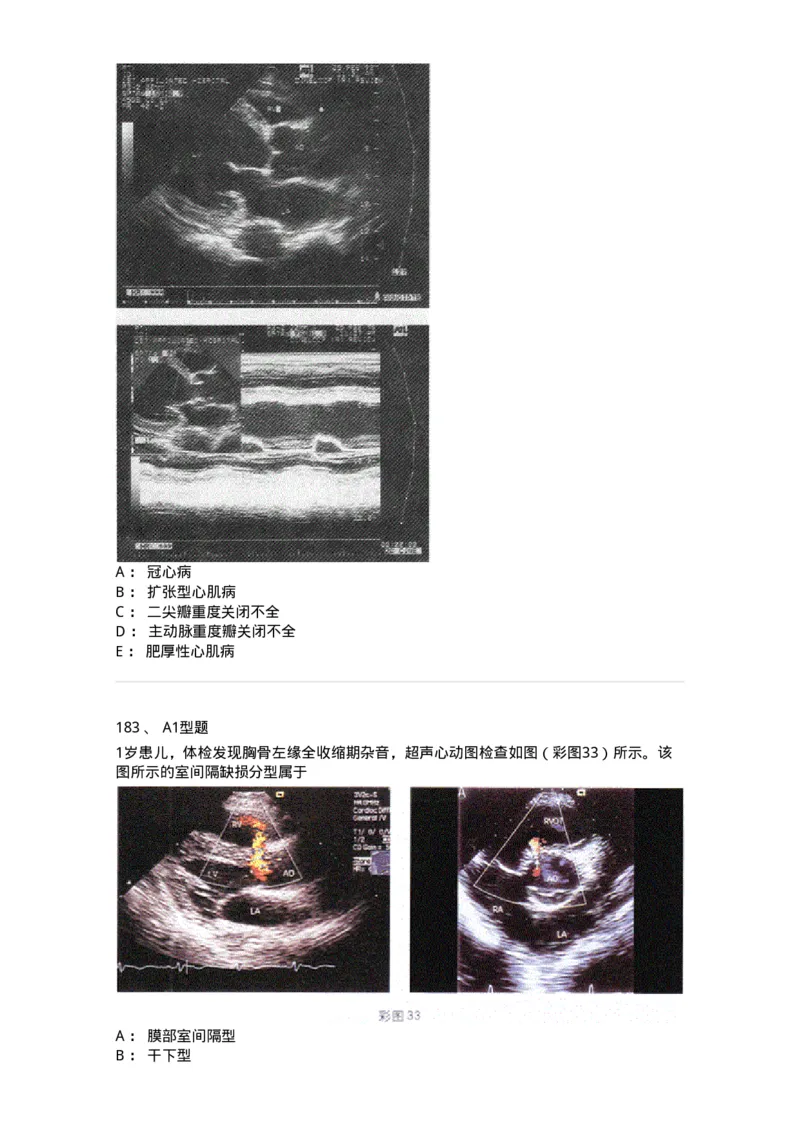

182 、 A1型题

患者感心悸、胸闷,过去无心脏病史,超声检查如图,最可能诊断A : 冠心病

183 、 A1型题

1岁患儿,体检发现胸骨左缘全收缩期杂音,超声心动图检查如图(彩图33)所示。该

图所示的室间隔缺损分型属于

A : 膜部室间隔型

B : 干下型C : 隔瓣下型

D : 肌部型

E : 嵴内型